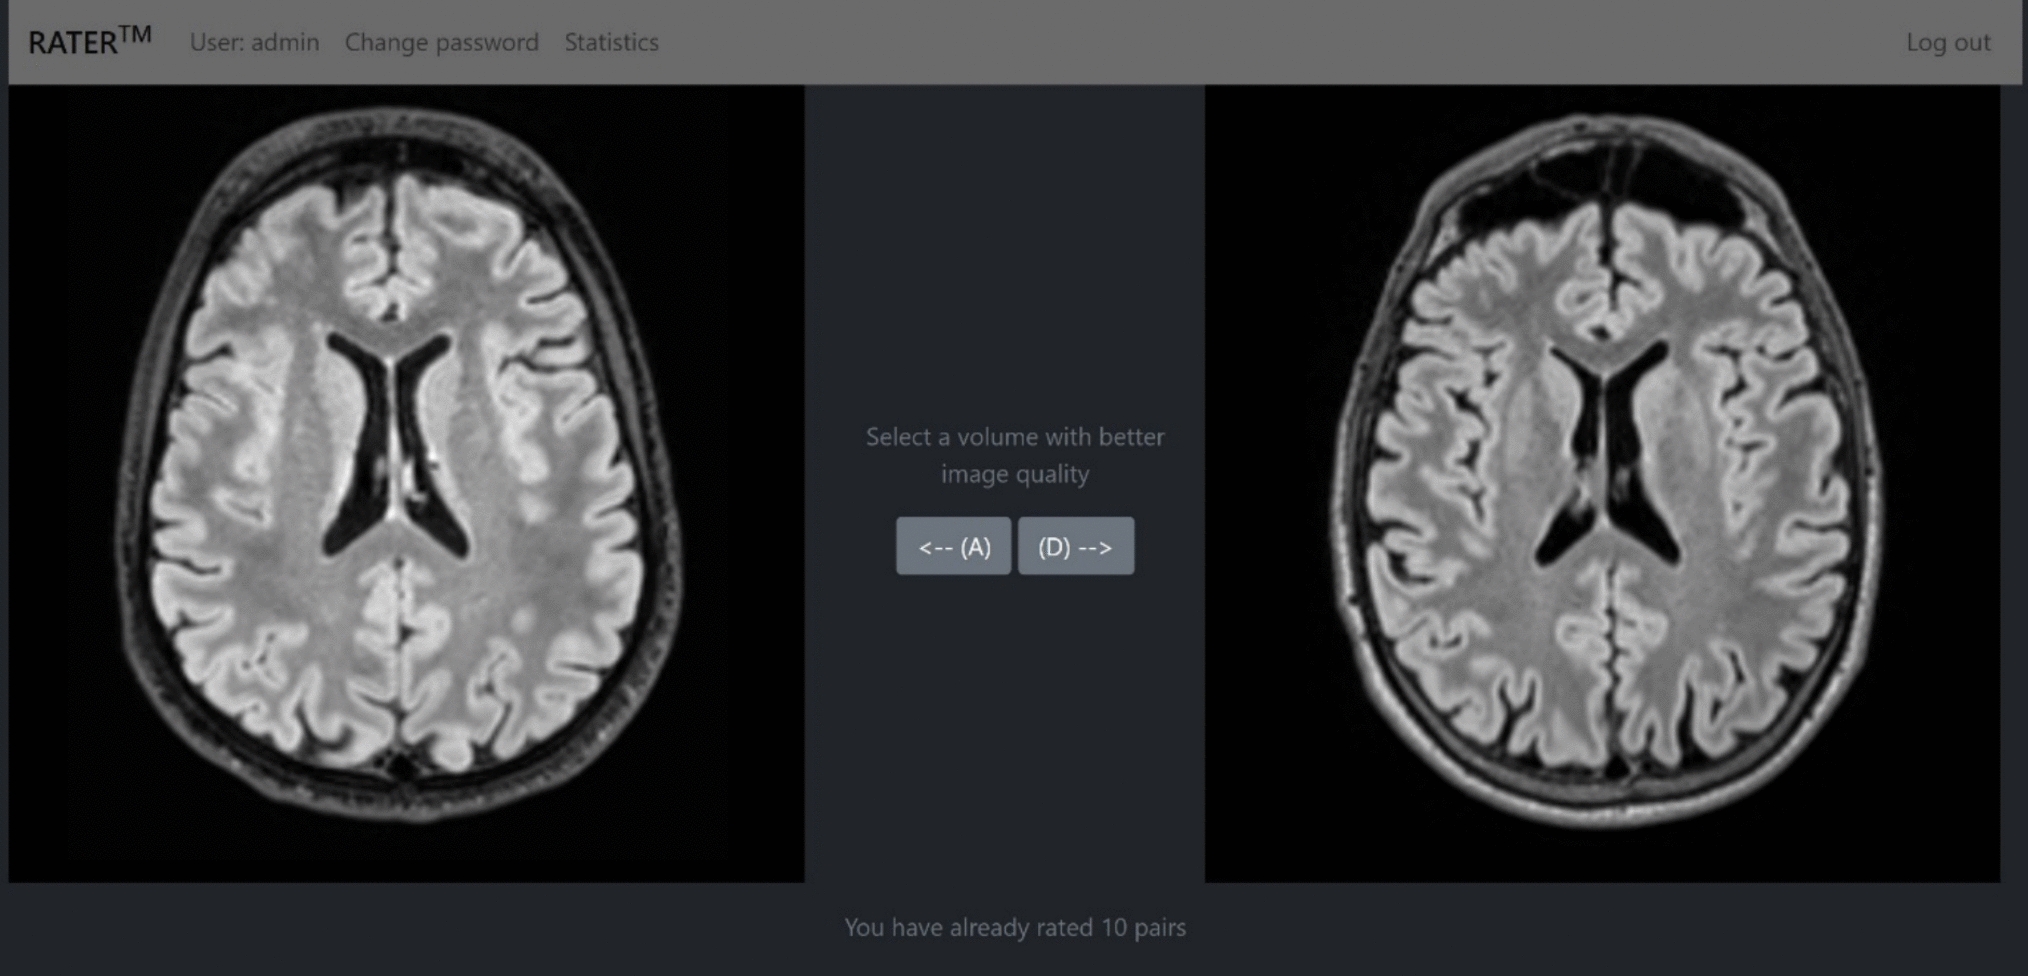

Fig. 2figure 2

The network structure of the ResUNet structure used in Deli + CS. The light gray boxes show the data size at various layers of the network, where the first three numbers are the spatial dimensions, and the fourth number is the number of feature channels. The convolutions with kernel size 1 in the skip connections match the input and output dimensions so that they can be added together after each convolutional layer